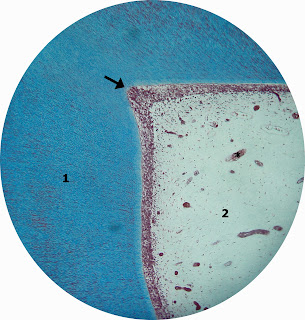

Técnica por descalcificação e coloração por Tricrômico de Mallory.

Detalhe da porção coronária e o corno pulpar:

1: Dentina coronária

2:Polpa

Seta: Corno pulpar

*: Vaso sanguíneo